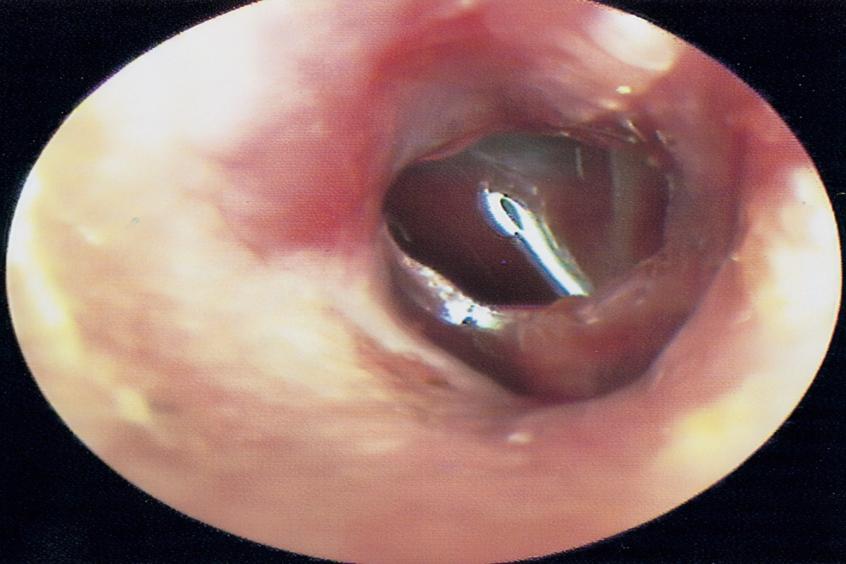

鼓膜,也称为耳膜,是一种弹性的灰色半透明膜,将外耳道与中耳分隔开来。它是一种椭圆形、浅灰色、半透明的薄膜,位于外耳道底部。鼓膜大部分附着在颞骨鼓部的沟上,上部附着在鳞部。附着在沟上的部分比较坚实,称为张力部分;附着在鳞片上的部分又薄又松,称为松弛。鼓膜向内凹陷,凹陷的尖端称为鼓脐膜。

鼓膜距离外耳道约2.5cm.5cm,位于外耳道和鼓室之间。鼓膜高约9mm,宽8mm,平均面积90mm2,厚0.1mm。鼓膜呈椭圆形,形状似漏斗,斜置于外耳道内,与外耳道形成45-50的基底。使得外耳道的后上壁比前下壁短。由于婴儿外耳道骨骼不发达,鼓膜几乎与外耳道底壁平行,检查时很难看到鼓膜。成人鼓膜长约9毫米,宽8毫米,厚0.1毫米。